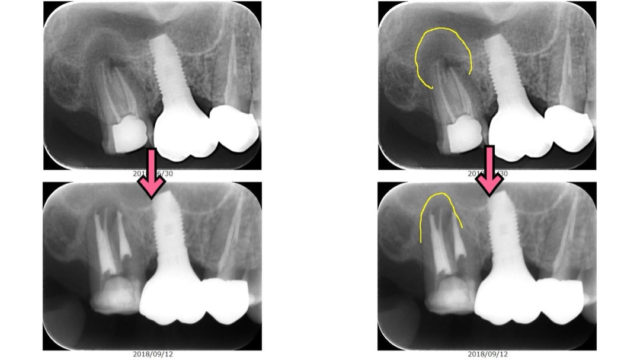

歯の根に膿が、根管治療で歯の温存を